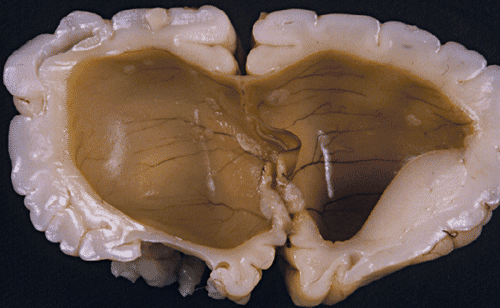

- Panel B: Medulloblastoma often lead to

obstruction of the flow of cerebral spinal fluid (CSF) and lead to

hydrocephalus.